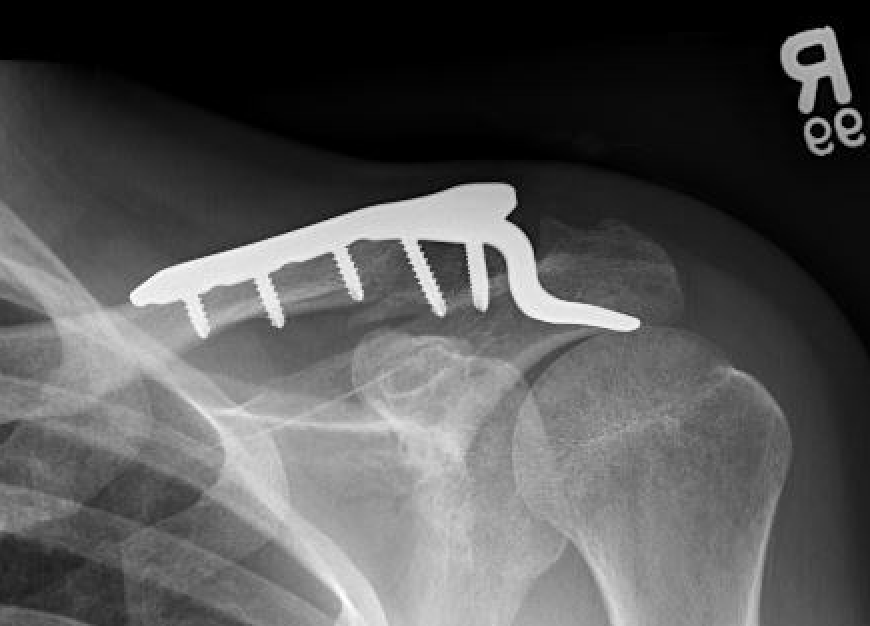

Dorsal locking plate +/- CC ligament reconstruction

Hook plate

Dorsal locking plate +/- CCL reconstruction

Advantage

No need to remove

Disadvantage

Lateral screws under significant tension and subsequently higher rate of screw/plate pull-out

Indication

Sufficient lateral bone to obtain fixation

Consider having hook plate available / supplement with coraco-clavicular fixation

Dorsal locking plate with cerclage fibretape

- precontoured distal locking plate in 35 patients

- all united at mean of 4 months

- excellent outcomes scores